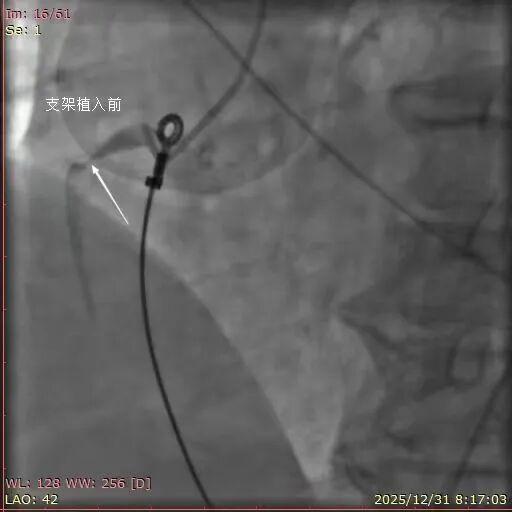

2025年12月31日,7点30分患者王某,女,57岁,突发胸痛10小时就诊于平度市第三人民医院胸痛中心,值班医生迅速为患者完善床旁心电图检查,检查结果提示“急性下壁心肌梗死”。与患者家属进行了充分沟通,并建议行急诊冠脉介入治疗。患者家属在了解情况后,毫不犹豫地同意并签字。随后,患者被送入导管室。术中造影结果显示:右冠状动脉近段99%狭窄,可见血栓影,TIMI血流2级。

与患者家属沟通并获得同意后,医护人员迅速为患者介入诊疗,成功在右冠近段置入4.0×23mm支架一枚。